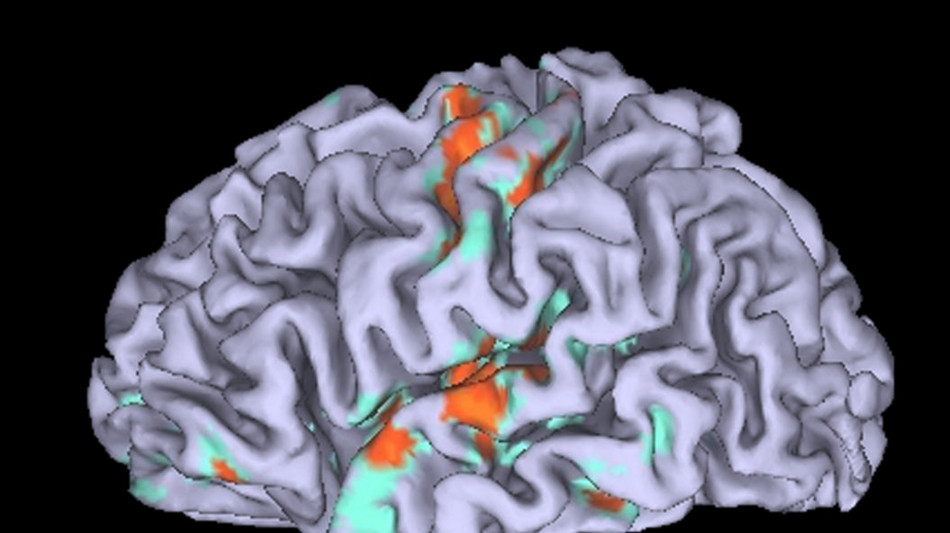

Individuata la regione del cervello dove nasce l'incoerenza morale di chi predica bene e razzola male: si tratta della corteccia prefrontale ventromediale (vmPFC), che ha il compito di integrare le informazioni pesando onestà e tornaconto personale per guidare le nostre azioni. Il risultato, che potrebbe avere importanti implicazioni per l'istruzione e l'intelligenza artificiale, è pubblicato sulla rivista Cell Reports dai ricercatori dell'Università della scienza e della tecnologia della Cina. "La coerenza morale è un processo biologico attivo", osserva il ricercatore Xiaochu Zhang. "Essere una 'persona morale' richiede che il cervello integri la conoscenza morale nel comportamento quotidiano, un processo che può fallire anche in persone che conoscono perfettamente il principio morale". Per identificare le regioni cerebrali associate all'incoerenza morale, i ricercatori hanno utilizzato la risonanza magnetica funzionale per scansionare il cervello di alcuni volontari durante un compito che richiedeva loro di valutare l'onestà e il profitto. I partecipanti potevano guadagnare più denaro essendo disonesti, ma dovevano anche valutare il proprio comportamento su una scala da 1 a 10 che andava da 'estremamente immorale' a 'estremamente morale'. Il team ha poi monitorato l'attività cerebrale dei partecipanti mentre giudicavano la moralità di altre persone impegnate nello stesso compito. Nelle persone moralmente coerenti, ovvero che giudicavano se stesse e gli altri secondo gli stessi standard morali, la corteccia vmPFC si attivava in modo simile sia durante il compito comportamentale che durante quello di giudizio. Tuttavia, nei partecipanti moralmente incoerenti (coloro che giudicavano immorale l'imbroglio altrui ma valutavano il proprio in modo più indulgente) la vmPFC risultava meno attiva durante il compito comportamentale e meno connessa alle regioni cerebrali coinvolte nel processo decisionale e nella moralità. Per scoprire se l'attività della vmPFC avesse un ruolo causale, i ricercatori l'hanno stimolata in alcuni partecipanti, tramite un metodo non invasivo chiamato stimolazione transcranica a interferenza temporale, prima che questi eseguissero compiti comportamentali e di giudizio. I risultati hanno dimostrato che la stimolazione della vmPFC ha portato a livelli più elevati di incoerenza morale. "Gli individui che mostrano incoerenza morale - sottolinea Zhan - non sono necessariamente ciechi ai propri principi morali; semplicemente, a livello biologico, non riescono a considerarli e applicarli nel proprio comportamento morale".